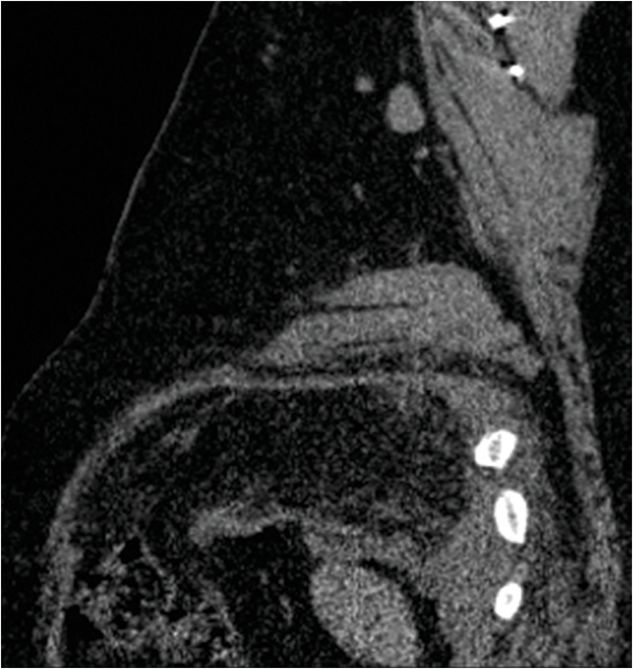

From radiologykey.com

59 45yearold male presenting with left upper quadrant pain and Pain In Upper Left Chest When Coughing The main symptom of pleurisy is sharp chest pain when you breathe in. Symptoms include sharp chest pain. The chest pain occurs when the irritated layers of the pericardium rub against each other. When chest pain from coughing is linked to a simple issue—like the common cold or allergies —it often improves when the cause is resolved. This can cause. Pain In Upper Left Chest When Coughing.